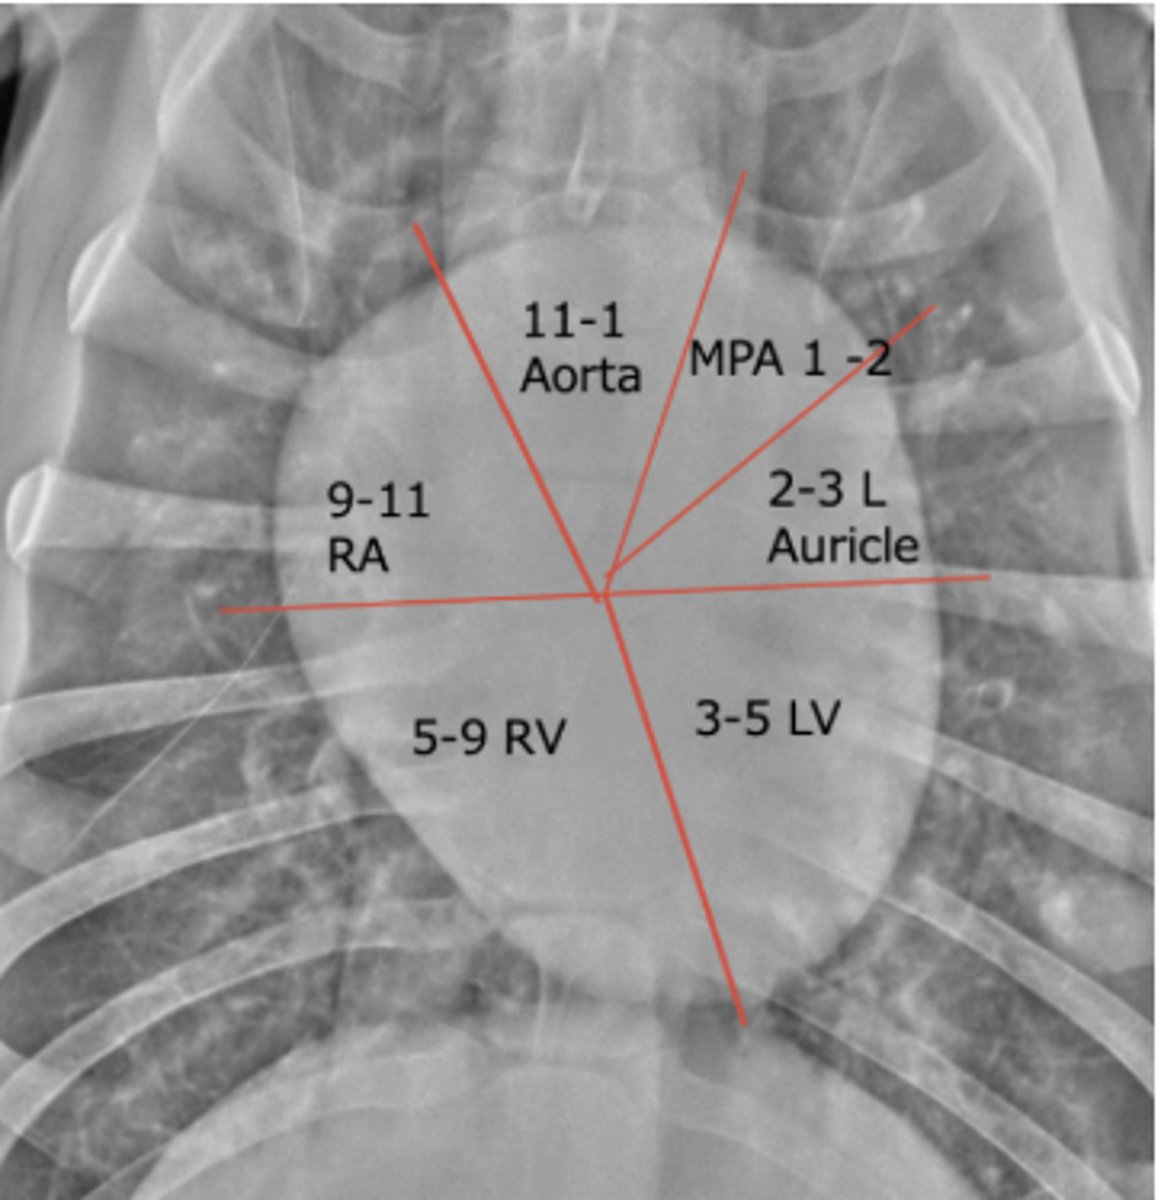

seen on the image

Where is the left ventricle